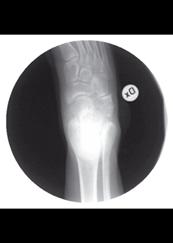

Risken att utveckla höftluxation hos barn med CP är 10-15%. Det är sedan mer än 50 år tillbaka känt att man i många fall kan förhindra uppkomsten av höftluxation med förebyggande behandling. I den förebyggande behandlingen ingår kontrakturprofylax med ortoser och bra positionering i liggande och sittande. Inte sällan krävs dessutom operation; adduktor-psoastenotomi, variserande proximal femurosteotomi och/eller bäckenosteotomi för att förhindra luxation (se Figur).

Figur 2. 5-årig pojke med CP. A. Röntgen visar lateralisering av caput i hö höft. B. Efter operation med variserande femurosteotomi.